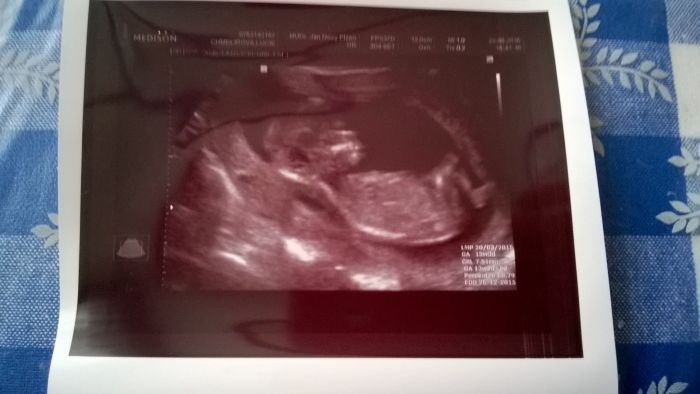

Tak holky všechno v pořádku, jak psala Veru - sice jsem byla u doktora co je přímo v baráku s mojí doktorkou,, ale podal ruku, změřil projasnění, kouknul na kůstku, ručičky, nožičky, žaludek, srdíčko, placenta, voda nazdar :-D ale jo říkal kde co vidím, pak začal do prcka šťouchat protože chtěl aby se otočil a to jsem se teda málem počůrala ... Říkal všechno ok, a krev a UTZ posílají na genetiku v Plzni. Obrázek přikládám. Jsem dneska šťastná jako blecha.

Jee Lucii krasnej prtousek ;-) Holky tak kocar to u me bude horsi vybirani pro dvojčátka neni takovej vyber, ale tak nejakej urco najdeme co se nam bude libit a bude pohodlnej.At uz je listopad :-D